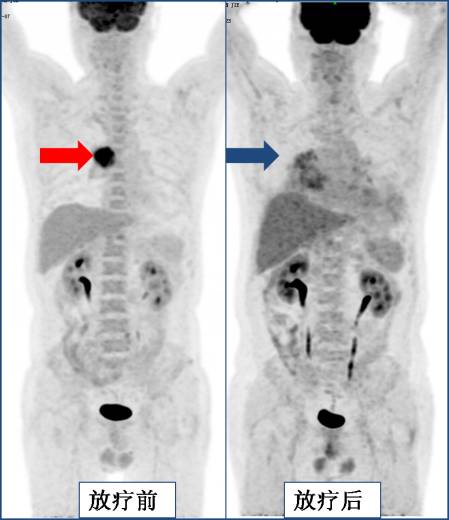

上图为肺癌放疗后,肿瘤消失,出现放射性肺炎。